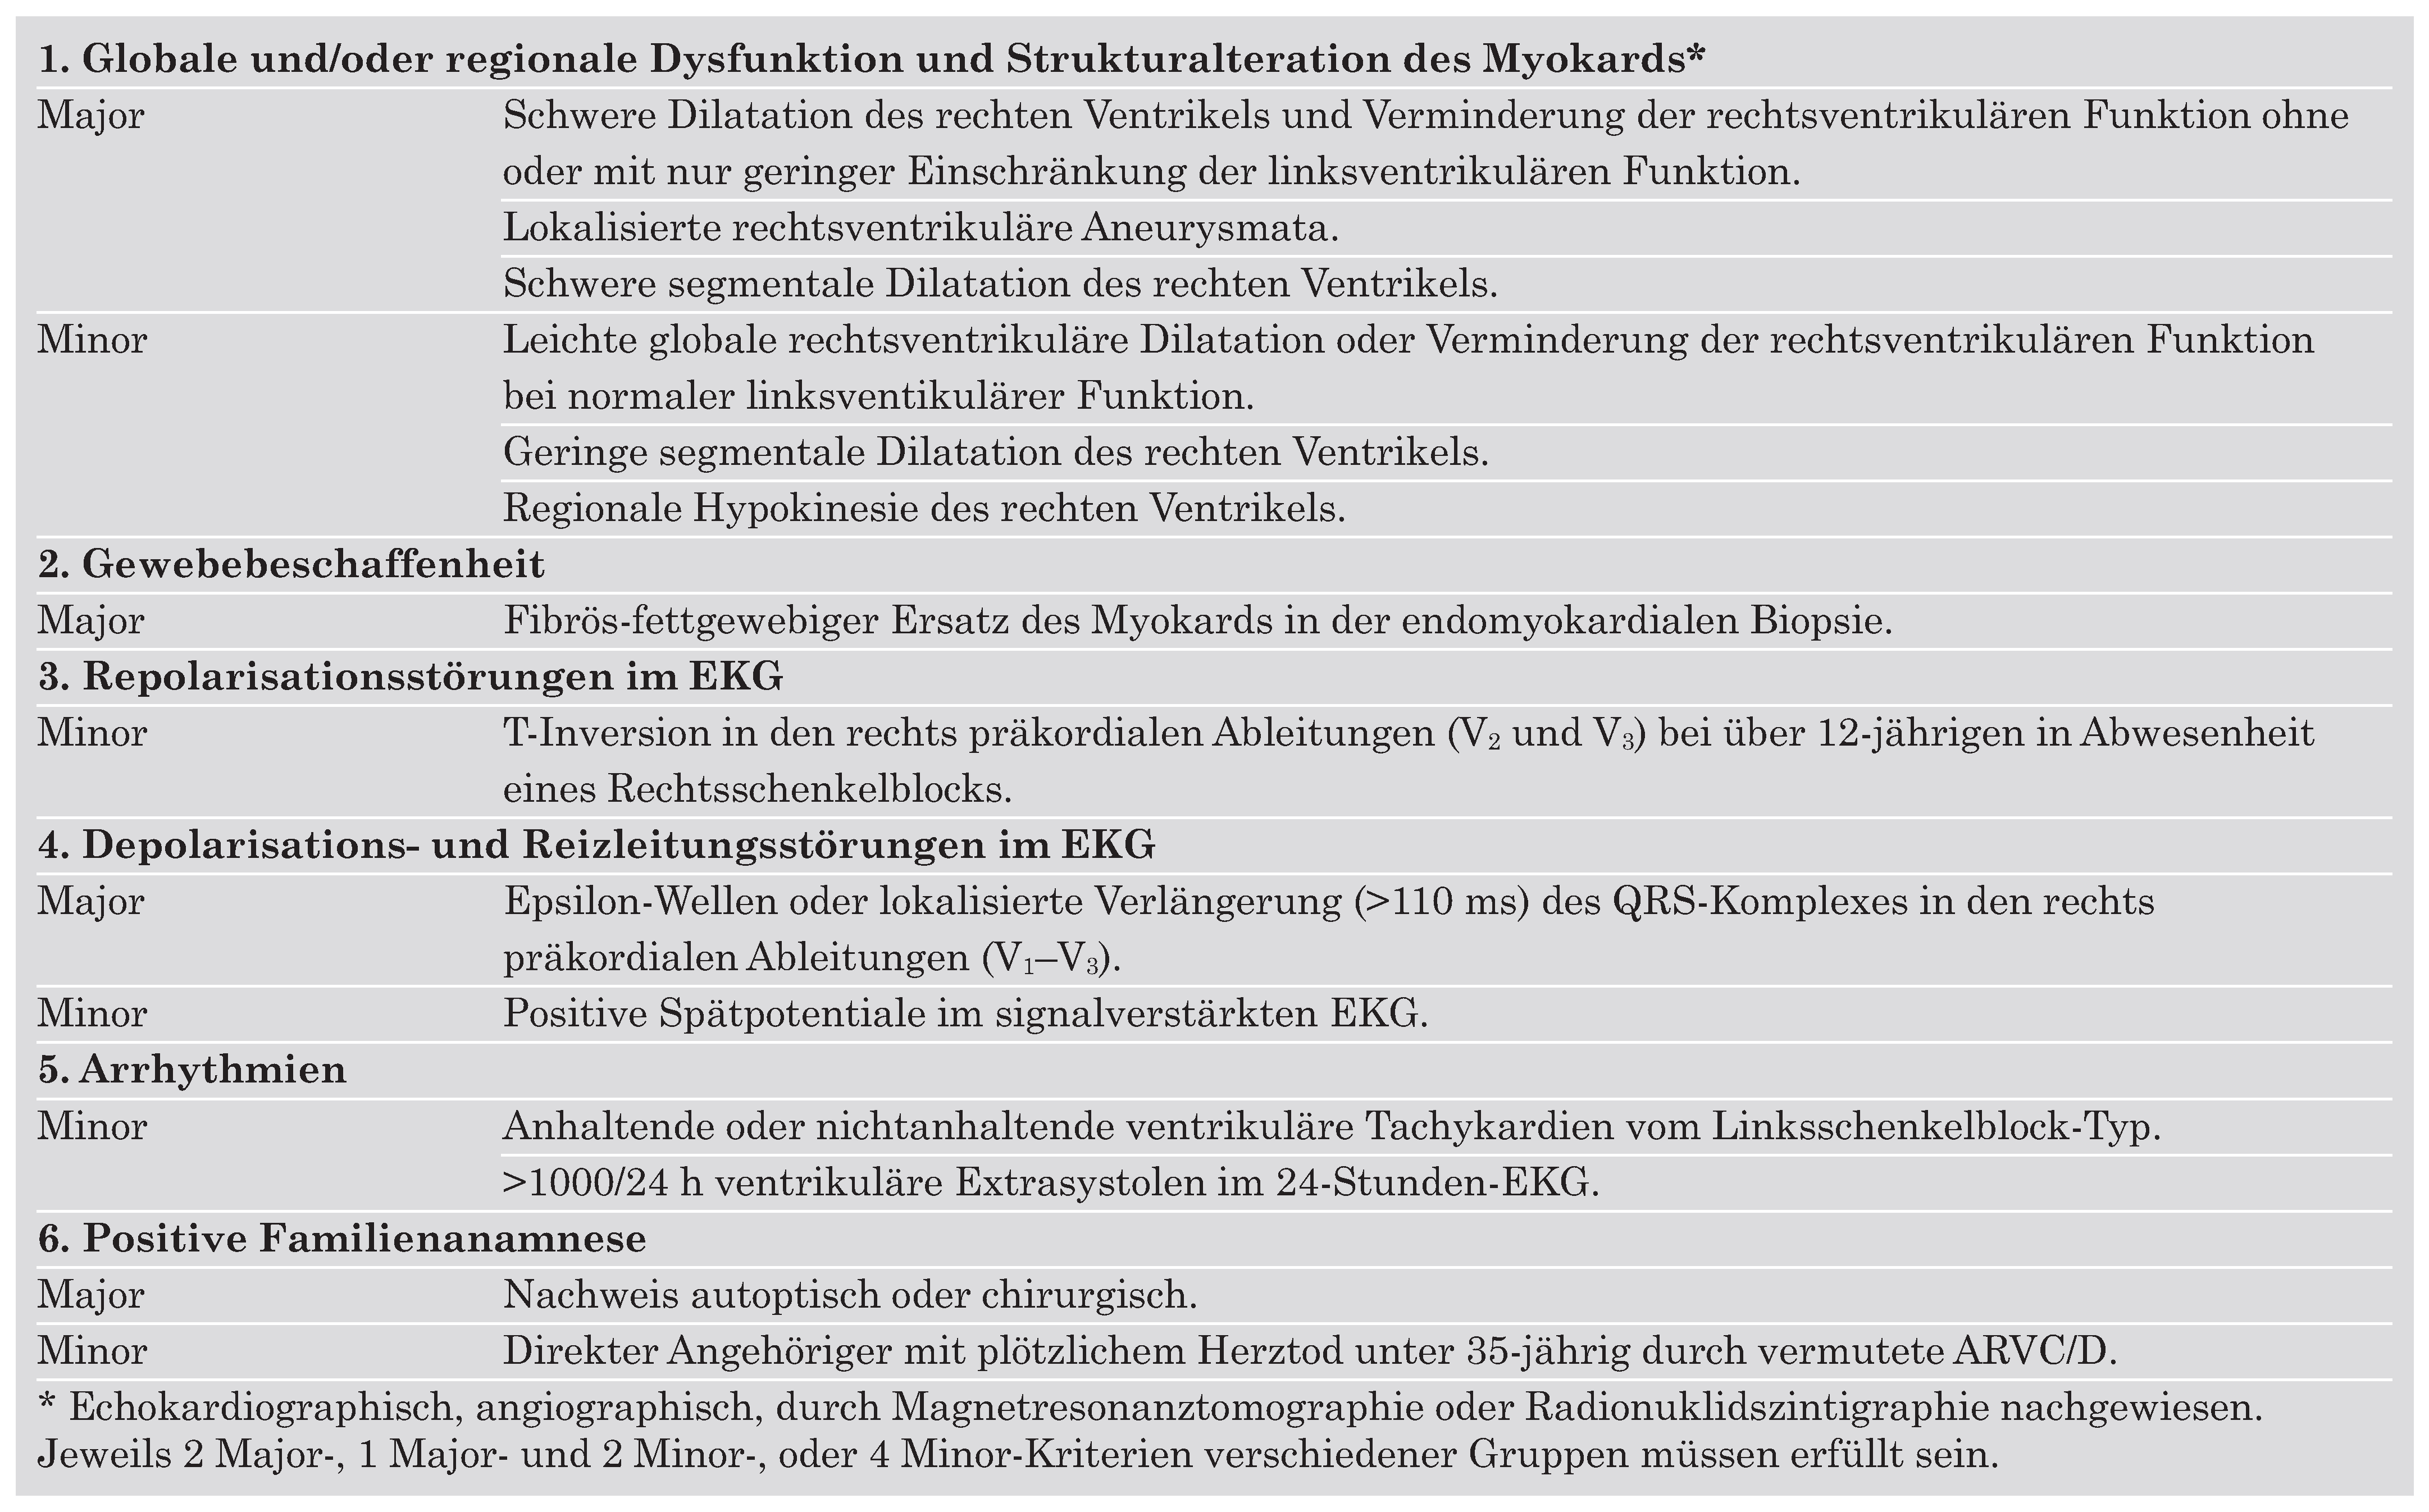

Ursprung der Extrasystolen

Fallbeschreibung

Diskussion